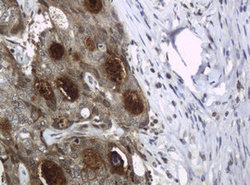

Supportive validation

- Submitted by

- antibodies-online (provider)

- Main image

- Experimental details

- Image(s): Immunohistochemistry